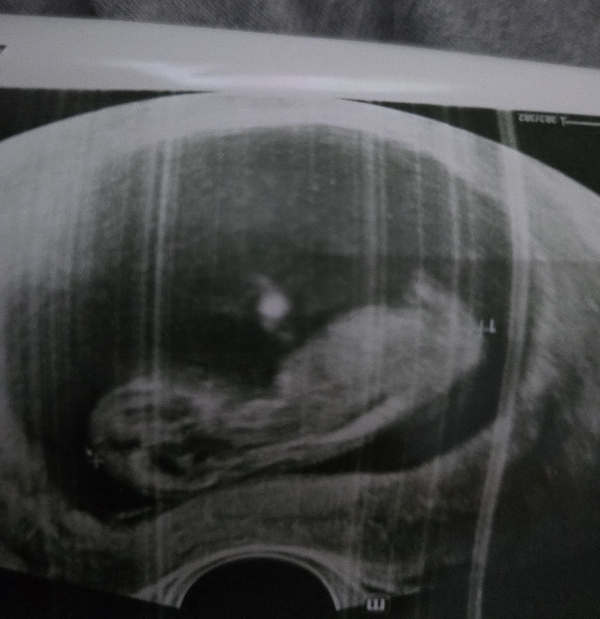

الحمل والإنجاب

اعرفي اعراض الحمل، متابعة شهور الحمل، تمارين الحمل، اعراض الولادة ، اصول الرضاعة الطبيعية